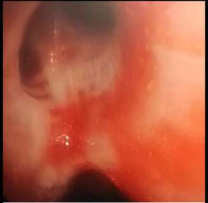

Figure 3: BAL for cytology in DAH

DAH usually presents with fever, haemoptysis, hypoxia, drop in haemoglobin although haemoptysis is present only in one third of the patients. Some patients present with acute onset breathlessness and requiring mechanical ventilation as described in the above case. CT picture shows bilateral ground glassing / consolidation which is diffuse. Recurrent DAH occurs in Idiopathic Pulmonary Hemosiderosis (IPH) resulting in pulmonary fibrosis later. DAH is usually associated with drop in haemoglobin, also since certain conditions are associated with renal damage like glomerulosclerosis, crescentic glomerulonephritis etc, hence associated with the elevation of serum creatinine. The characteristic bronchoscopy picture shows intra bronchial bleeding and sequential progressive haemorrhagic BAL sample. The definitive diagnosis is done by cytology which shows hemosiderin laden macrophages on Prussian blue stain . DLCO will be increased in DAH in stable patients if it can be performed.

BAL is an important diagnostic tool for DAH. Bronchoscopy usually reveals progressive haemorrhagic BAL. BAL cytology may sometime reveal hemoisiderin laden macrophages. BAL is also important in severe ARDS since it helps in diagnosing any associated viral, parasitic or bacterial illness.